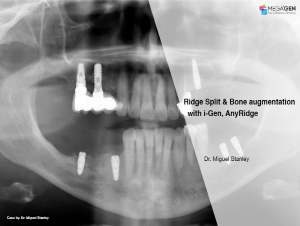

Keywords

e.g. product name, treatment solution, author, clinician name